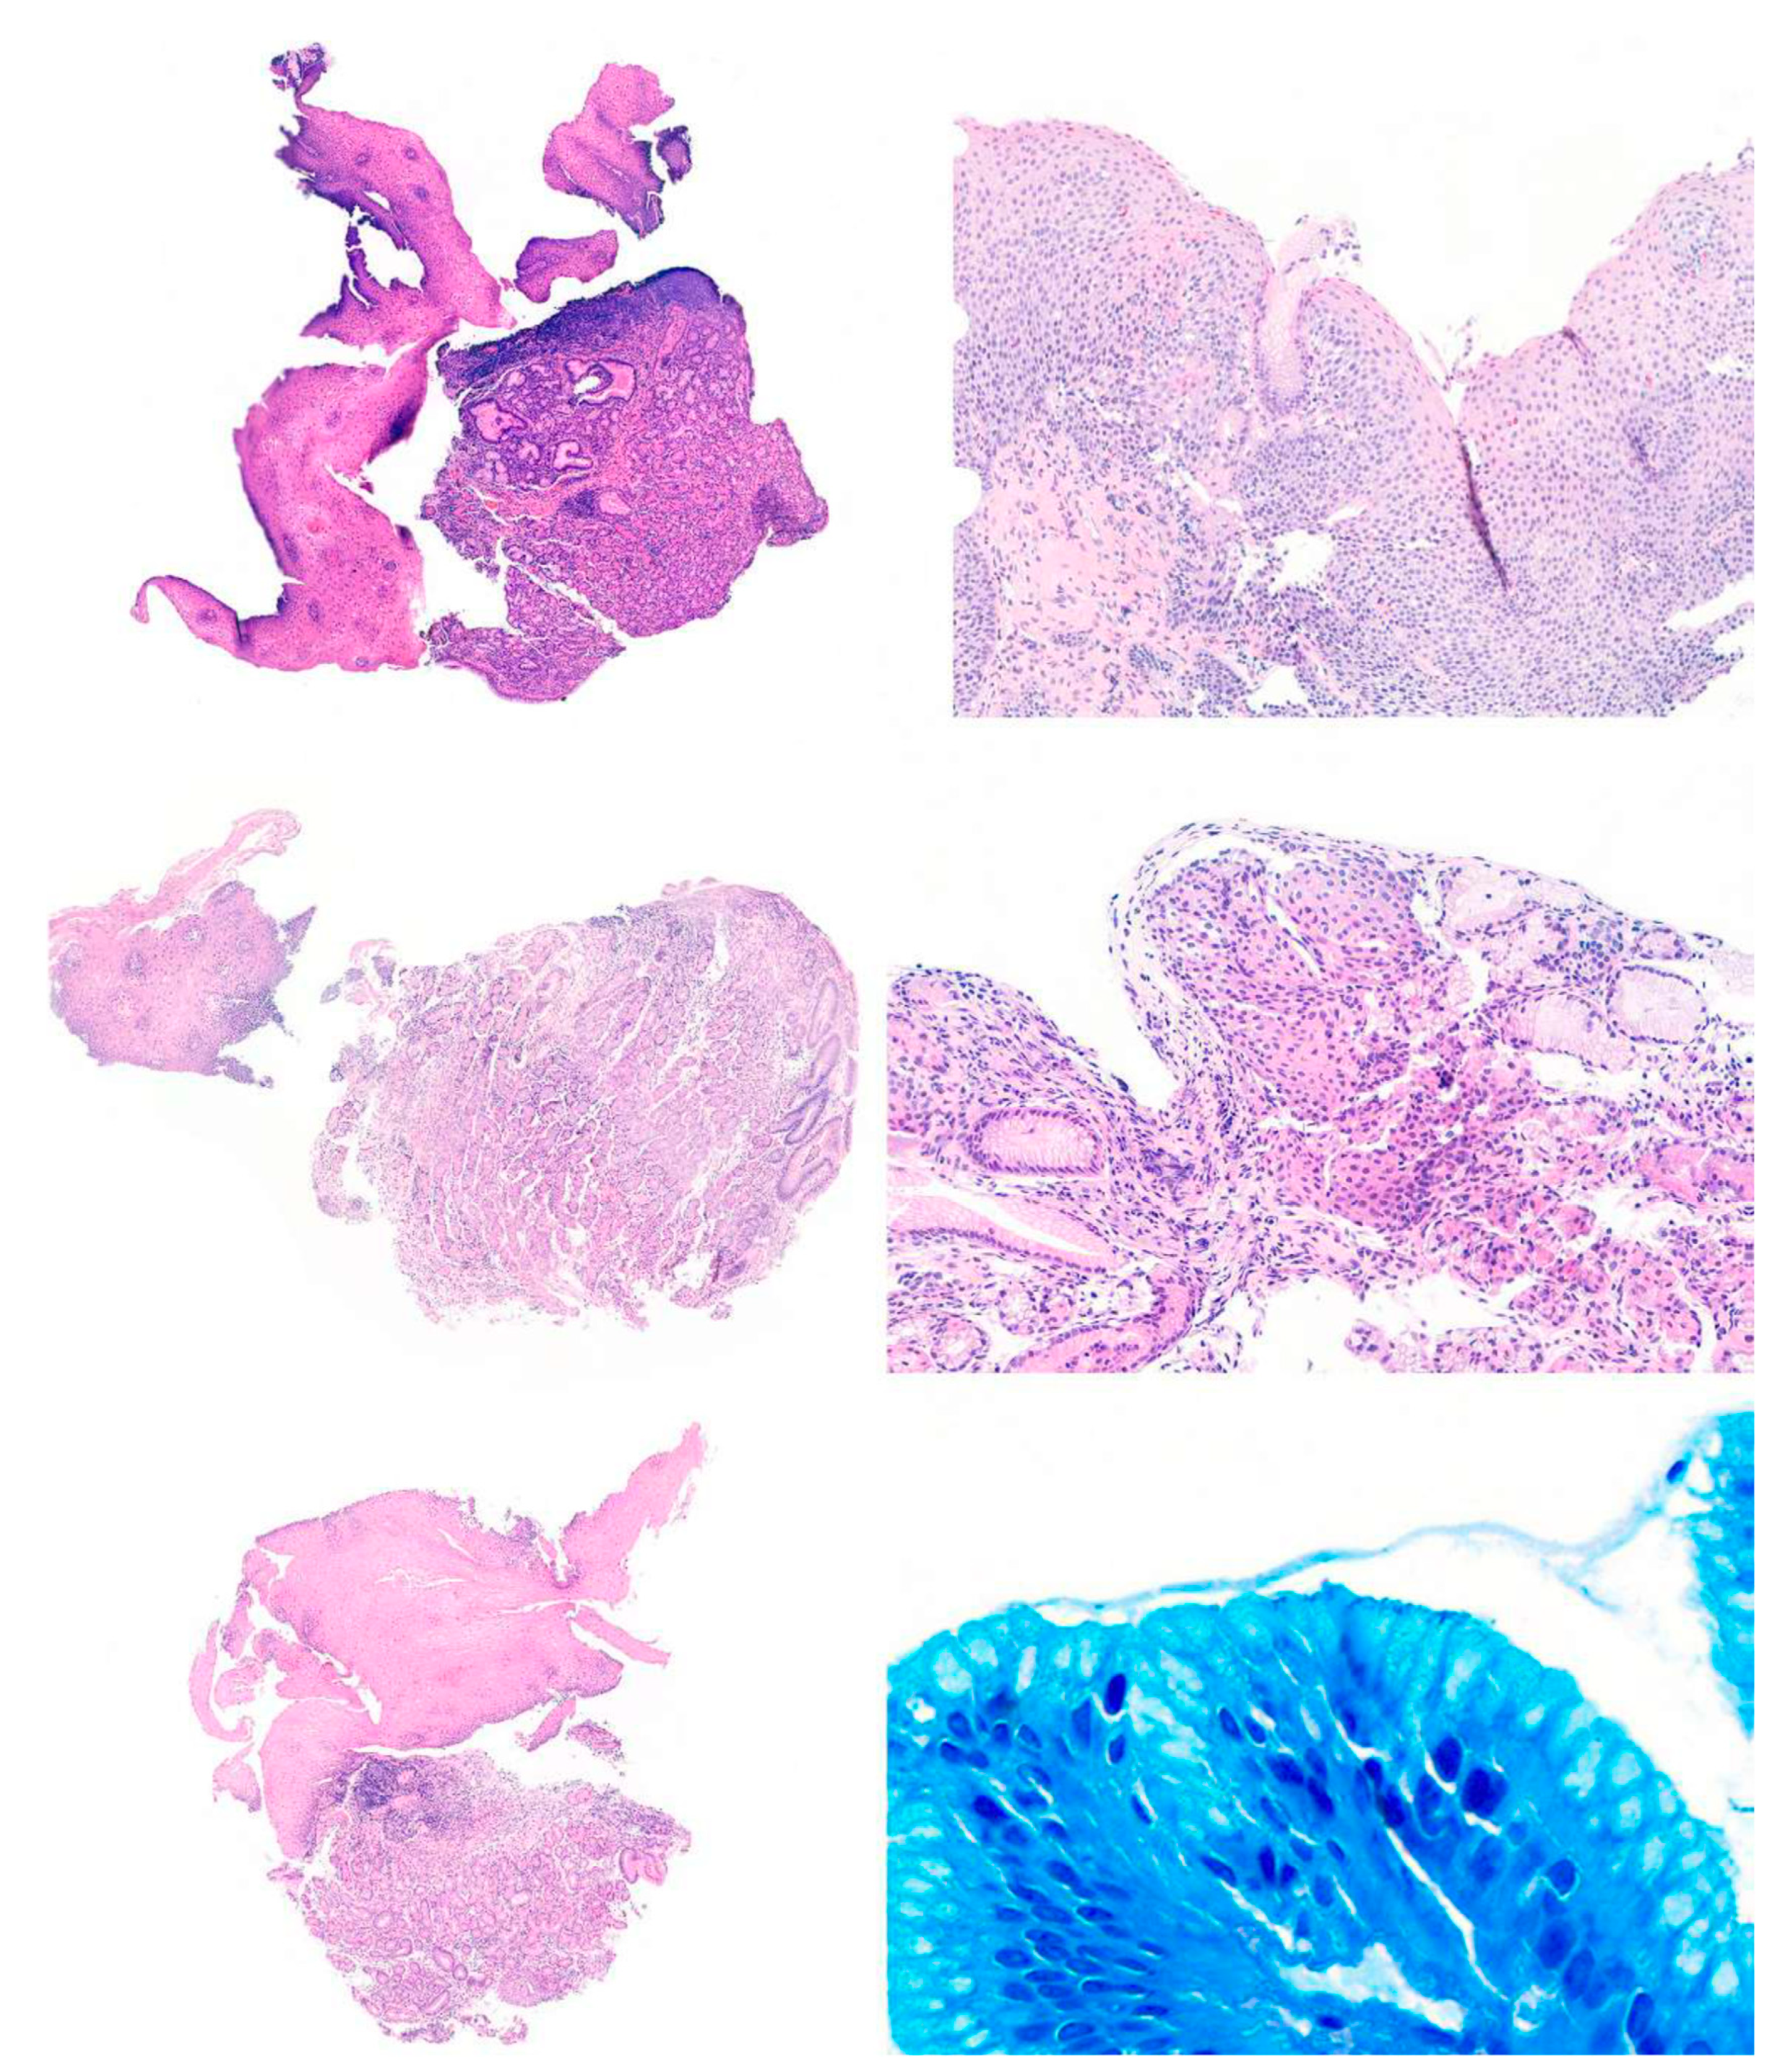

![]() |